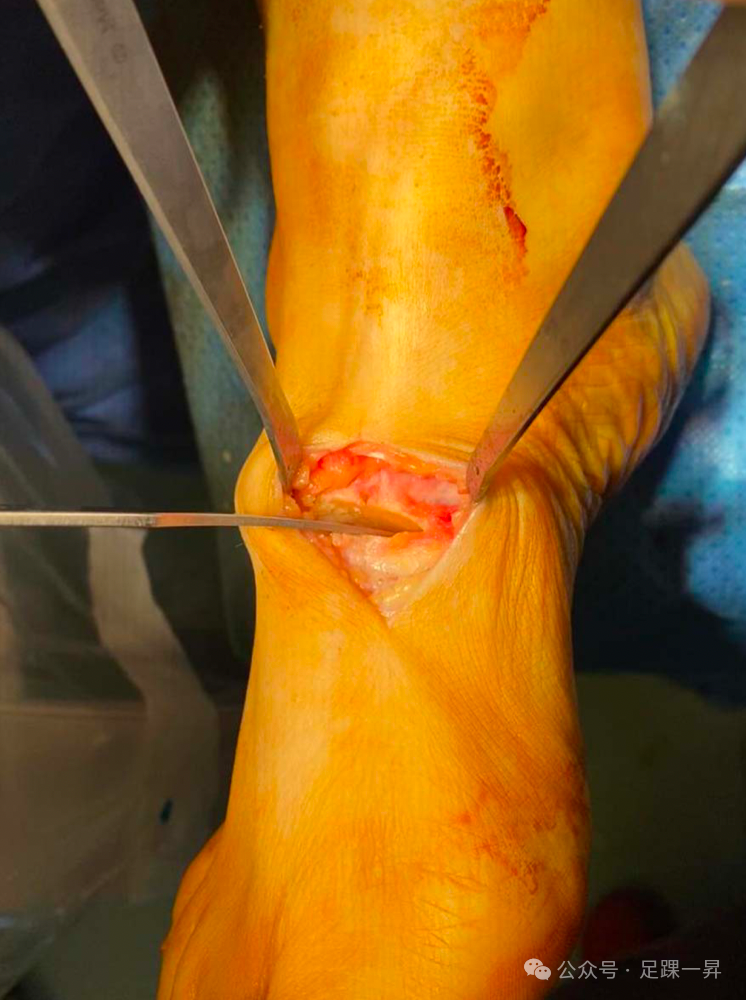

高弓足顾名思义指的是侧面观足弓高企,在行走或者负重过程中过程失去弹性,不能相对变平,从而不能完成正常站立和行走功能。